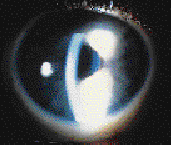

Contact Lens Induced Acute Red Eye

Contact lens induced acute red eye (CLARE) reaction is also identified as "tight lens syndrome." Onset is sudden, usually upon awakening, with pain, tearing and photophobia. Clinical presentation includes conjunctival and limbal hyperemia, and subepithelial infiltrates (Fig. 3). CLARE is an acute inflammatory response to toxic substances released by post-lens cellular debris breakdown in the closed-eye environment during hydrogel lens extended wear.

|

Advise patients to immediately discontinue lens wear until resolution. There is a 50 percent chance of recurrence if extended wear is resumed. In order to minimize the possibility of developing a CLARE reaction, refit the patient into a lens with sufficient movement to remove debris behind the lens, and emphasize mechanical and enzymatic cleaning.